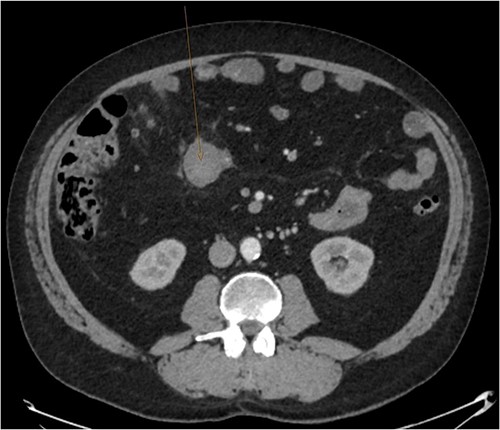

A CT abdomen-pelvis (CT-AP) revealed an acute haematoma inferolateral to the third part of the duodenum and another at the root of the mesentery. High density fluid related to the mesenteric bleed was also seen extending from the right para-colic gutter into the pelvis and in the peri-hepatic region. The patient was admitted under general surgery, stabilized with intra-venous fluid resuscitation, co-amoxiclav and metronidazole and cross matched for four units of blood. A CT-angiogram demonstrated acute haemorrhage throughout the abdomen with a 104 x 62 mm haematoma arising centrally at the level of L2 within the mesenteric fat (Fig. 1). The haematoma did not appear to originate from any specific mesenteric vessels but was related to some mid and distal jejunal loops. The angiogram also showed discontinuity when tracing the proximal and mid jejunal loops inferiorly, extensive haemorrhagic peritoneal fluid around the liver extending inferiorly (Fig. 2) and a small amount of peri-splenic haemorrhagic fluid. Curved reformatting of the angiogram revealed no abnormalities within the superior mesenteric artery (Fig. 3).

CT angiogram showing a large acute mesenteric haematoma. Figure 1 is taken from an axial section of the patient’s initial CT angiogram of the abdomen and pelvis. The arrow shown highlights an area of high-density fluid representing a 104 x 62 mm acute mesenteric haematoma.